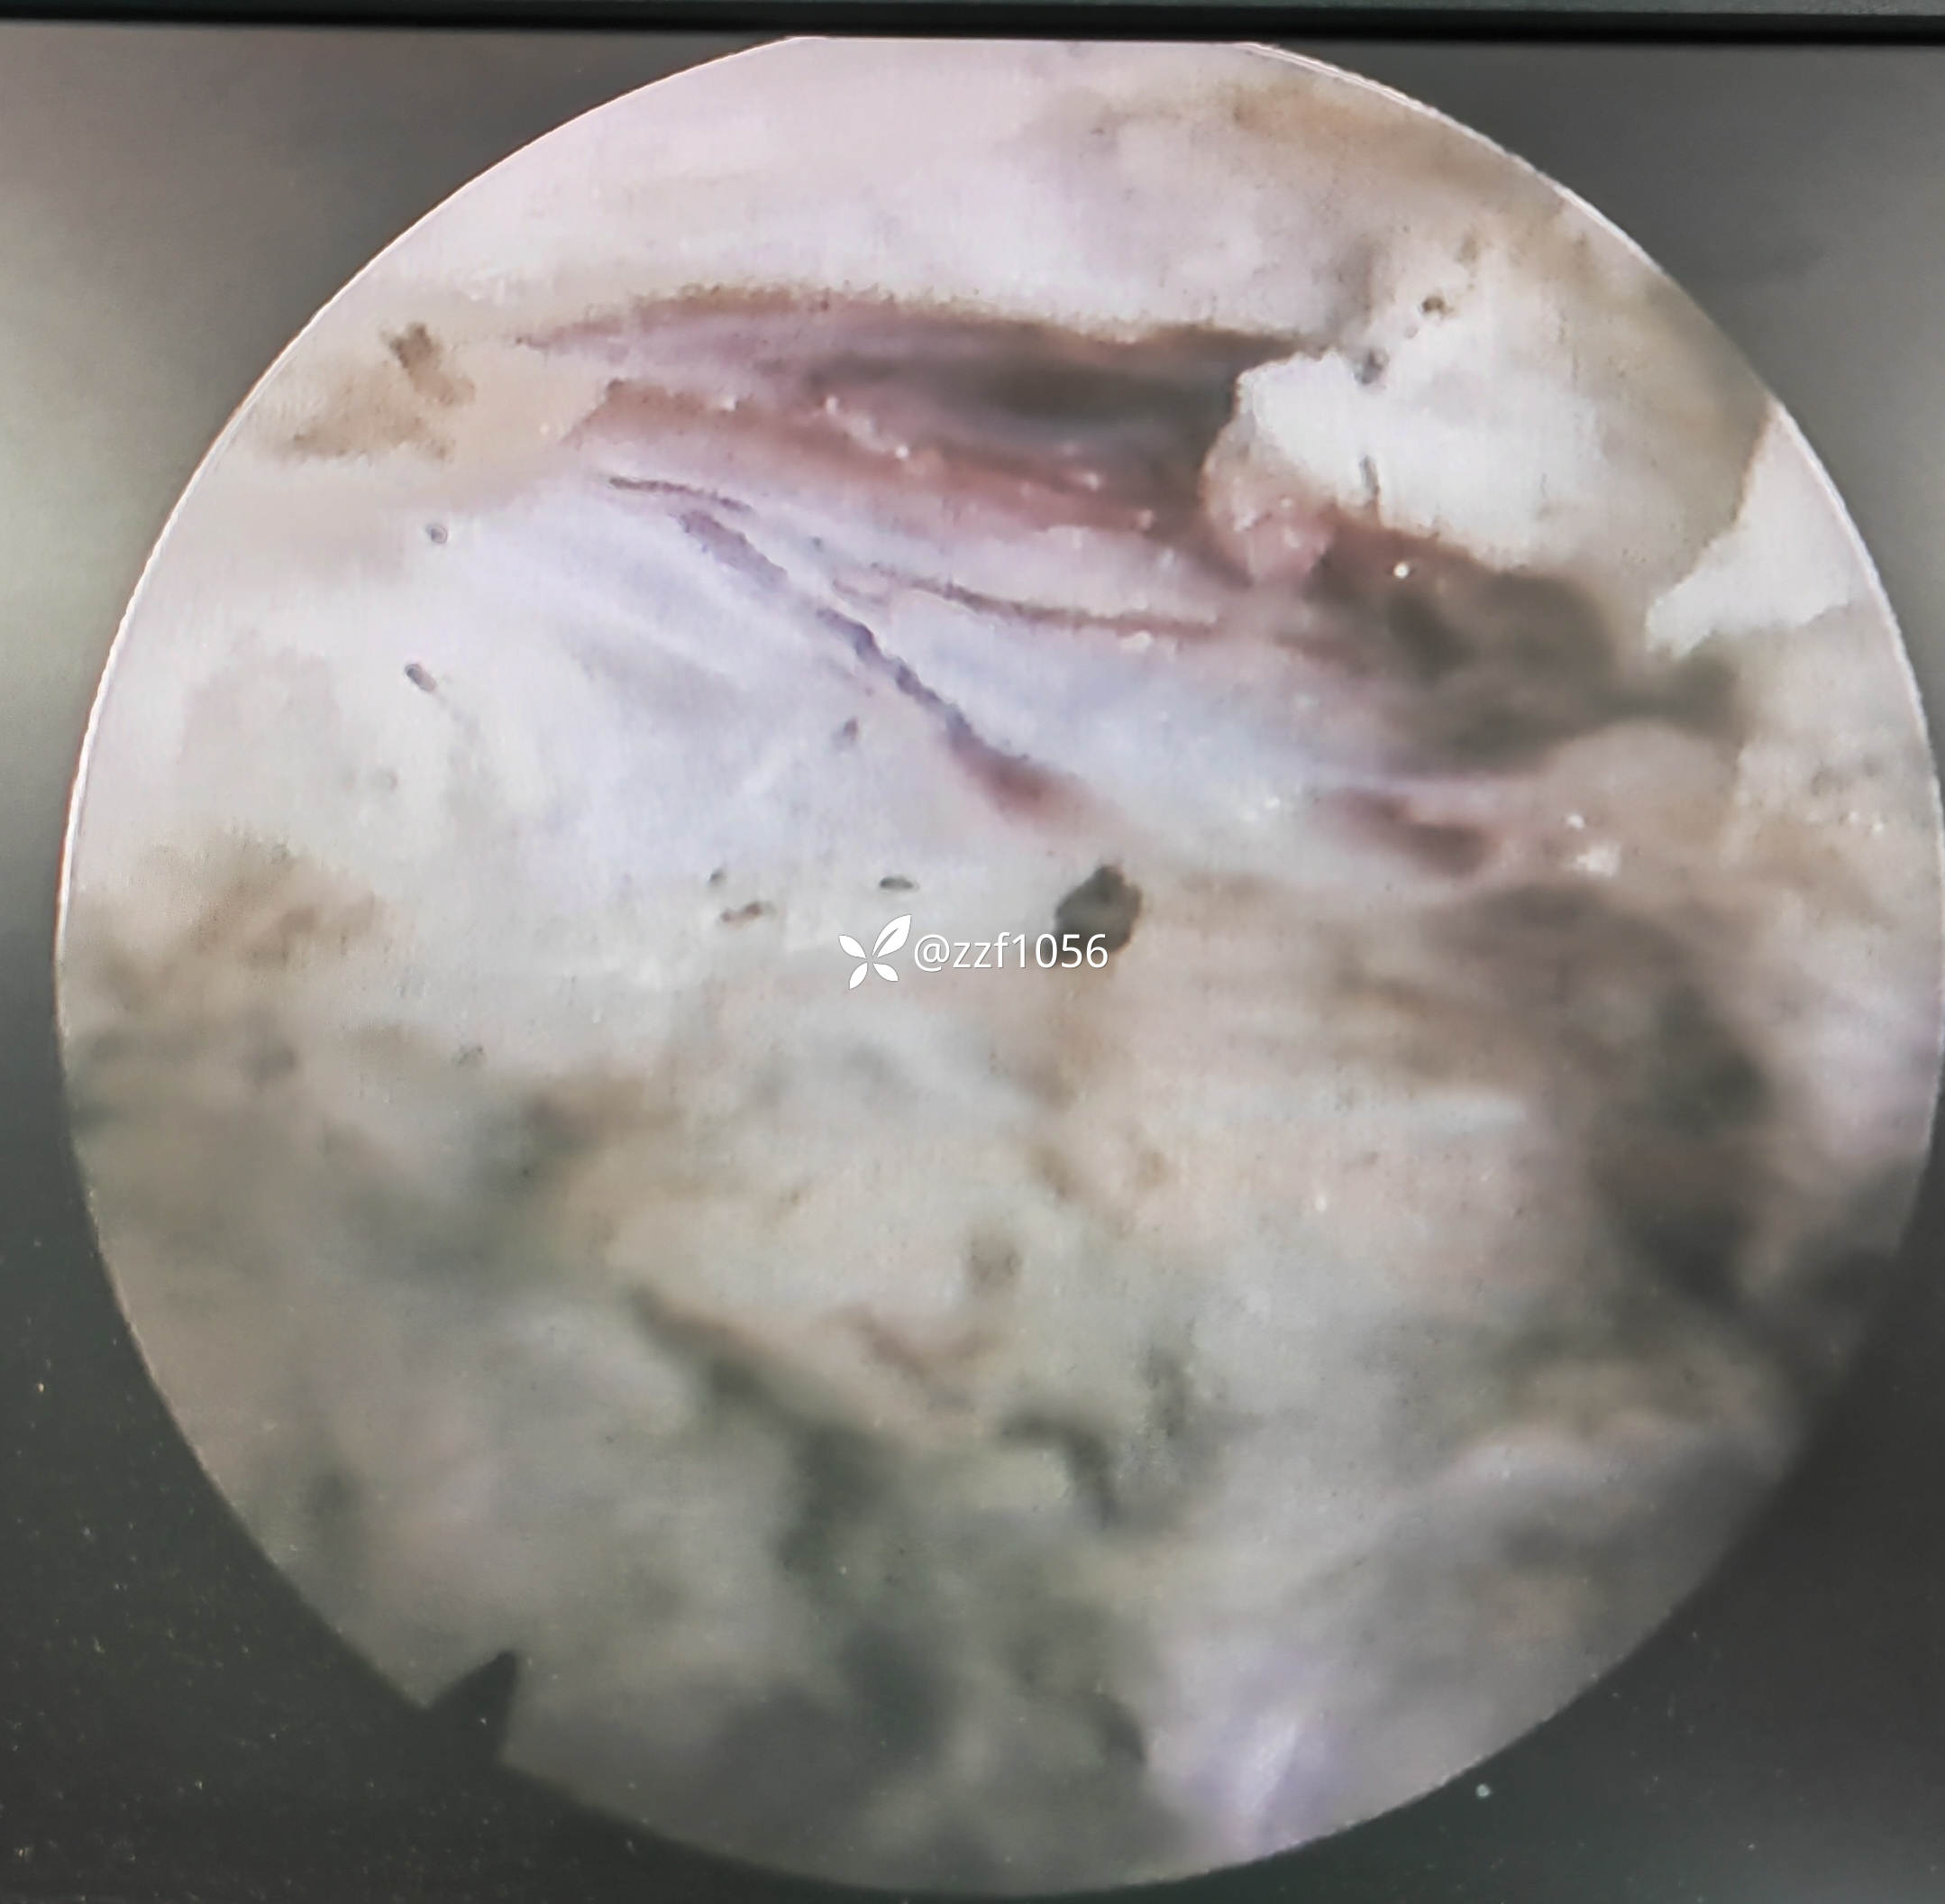

侧隐窝处神经根被髓核挤压较重

取出挤压神经根部髓核